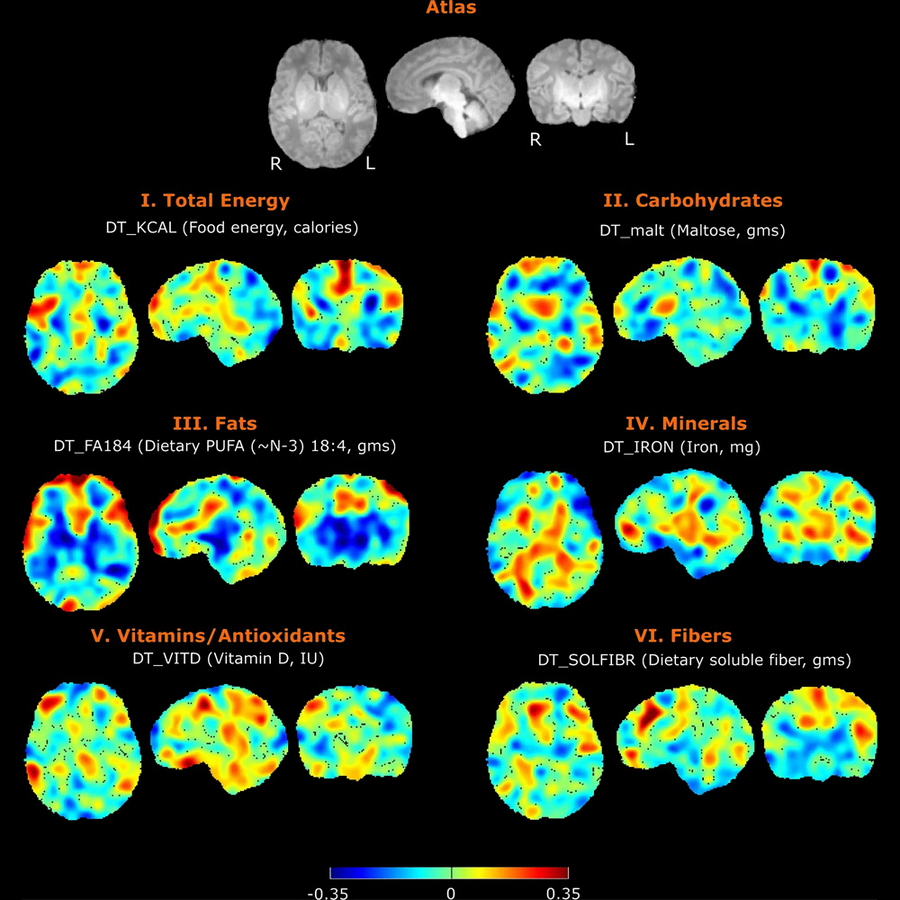

Nutrition has profound impact on neurodevelopment, but the mechanisms are only partly understood. In collaboration with other researchers at the Fetal-Neonatal Neuroimaging Developmental Science Center, we are studying the connections between maternal diet, breastmilk contents, infant brain development and child neurodevelopment. We also have a pilot study on the trajectory of infant develop the important skill of oral feeding with the goal of improving diagnosis and personalized care through quantitative EMG assessment of infant feeding, advanced computational analytics, and identifying biomarkers of neonatal outcomes.